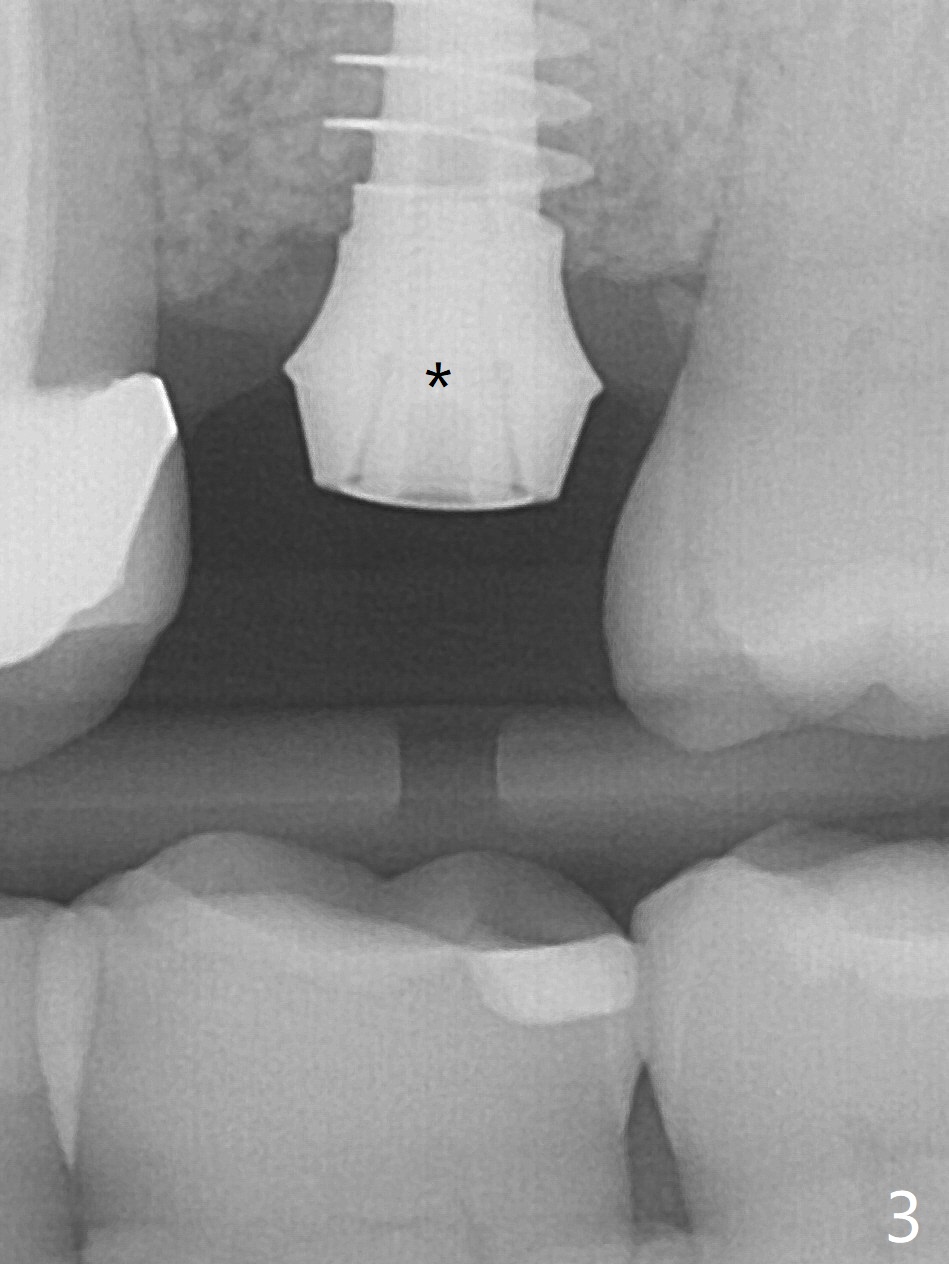

The ridge is wide at #14 11 months post socket preservation. Access and bone expansion (BEB) starts with Magic Split, followed by Magic Expanders 3.0, 3.8 and 4.3 mm from 8 to 9 mm for sinus lift. No bone is removed for osteotomy. Instead bone condensation occurs. After placement of a 4.5x11 mm dummy FC implant (Fig.1 with sinus lift (without bone graft)), a 5x9(2) mm Magicore (2 mm cuff) is placed with >55 Ncm with cuff margin at the gingival margin (Fig.2); a 5.5x3 mm solid abutment tries in. There is no occlusal clearance; trimming of the solid abutment will be needed. Later a healing screw is placed (Fig.3 *). There is no bone loss 5.5 months postop (Fig.4). A healing cap is placed without much tissue blanching. Instead a 5.5x3 mm solid abutment is placed; after height adjustment, impression is taken. A permanent crown is temporarily cemented 6 months postop (to rule out food impaction) and permanently re-cemented 7 months postop (Fig.5,6). CBCT taken 3-4 months post cementation shows that the implant threads are within the bone (Fig.7) and that the implant barely enters the sinus (Fig.8 *). That is significant since the patient has chronic sinusitis with thickened sinus membrane (Fig.9 *). The tooth #18 seems to have crazing line 10 months post cementation of the crown at #14 (overloading, Fig.10).